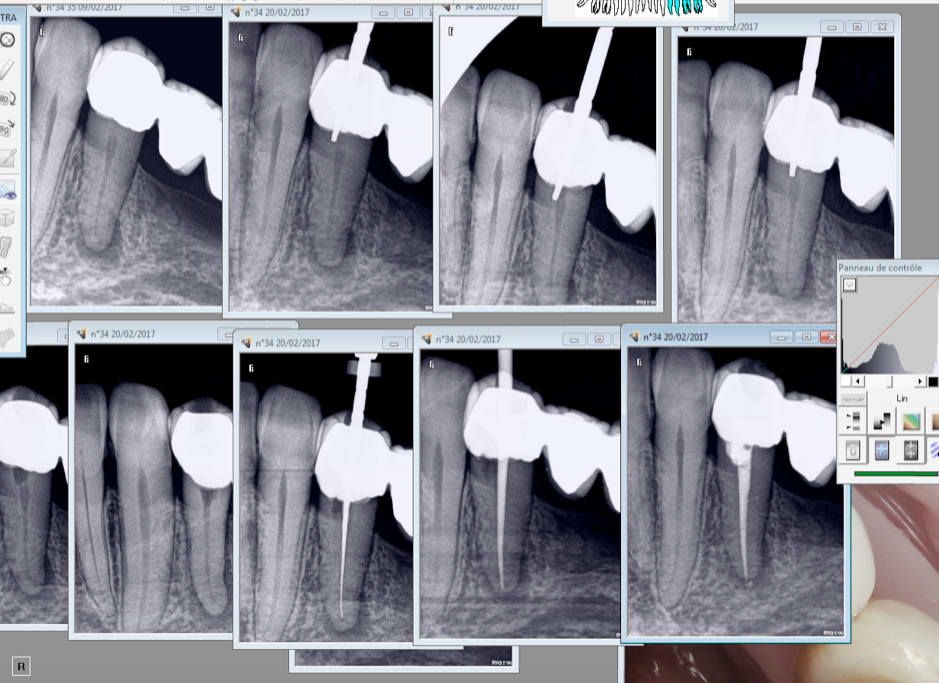

C'est la pulpe c'est la pulpe.

Putain j'ai eu chaud. -) vestibulaire ? Lingual ? vestibulaire lingual ?........Lingual !

Capture d écran 2017 02 20 16.51 - Eugenol

Capture d écran 2017 02 20 17.06 - Eugenol

Il y a un truc bizarre, sur tes RX on a l'impression que l'orifice du canal est distalisé,un peu comme la lésion apicale et ton obturation et plus dans l'axe, un artefact probablement.

sans radio ni avant ni pendant ni de suite apres .

tout au toc-toc et lentulo + cone +spaden , aille pas taper :-)))